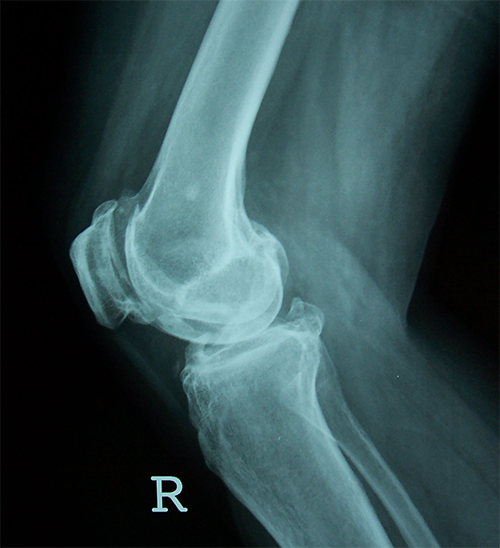

Case:2 TKR

Pre-Op Lateral